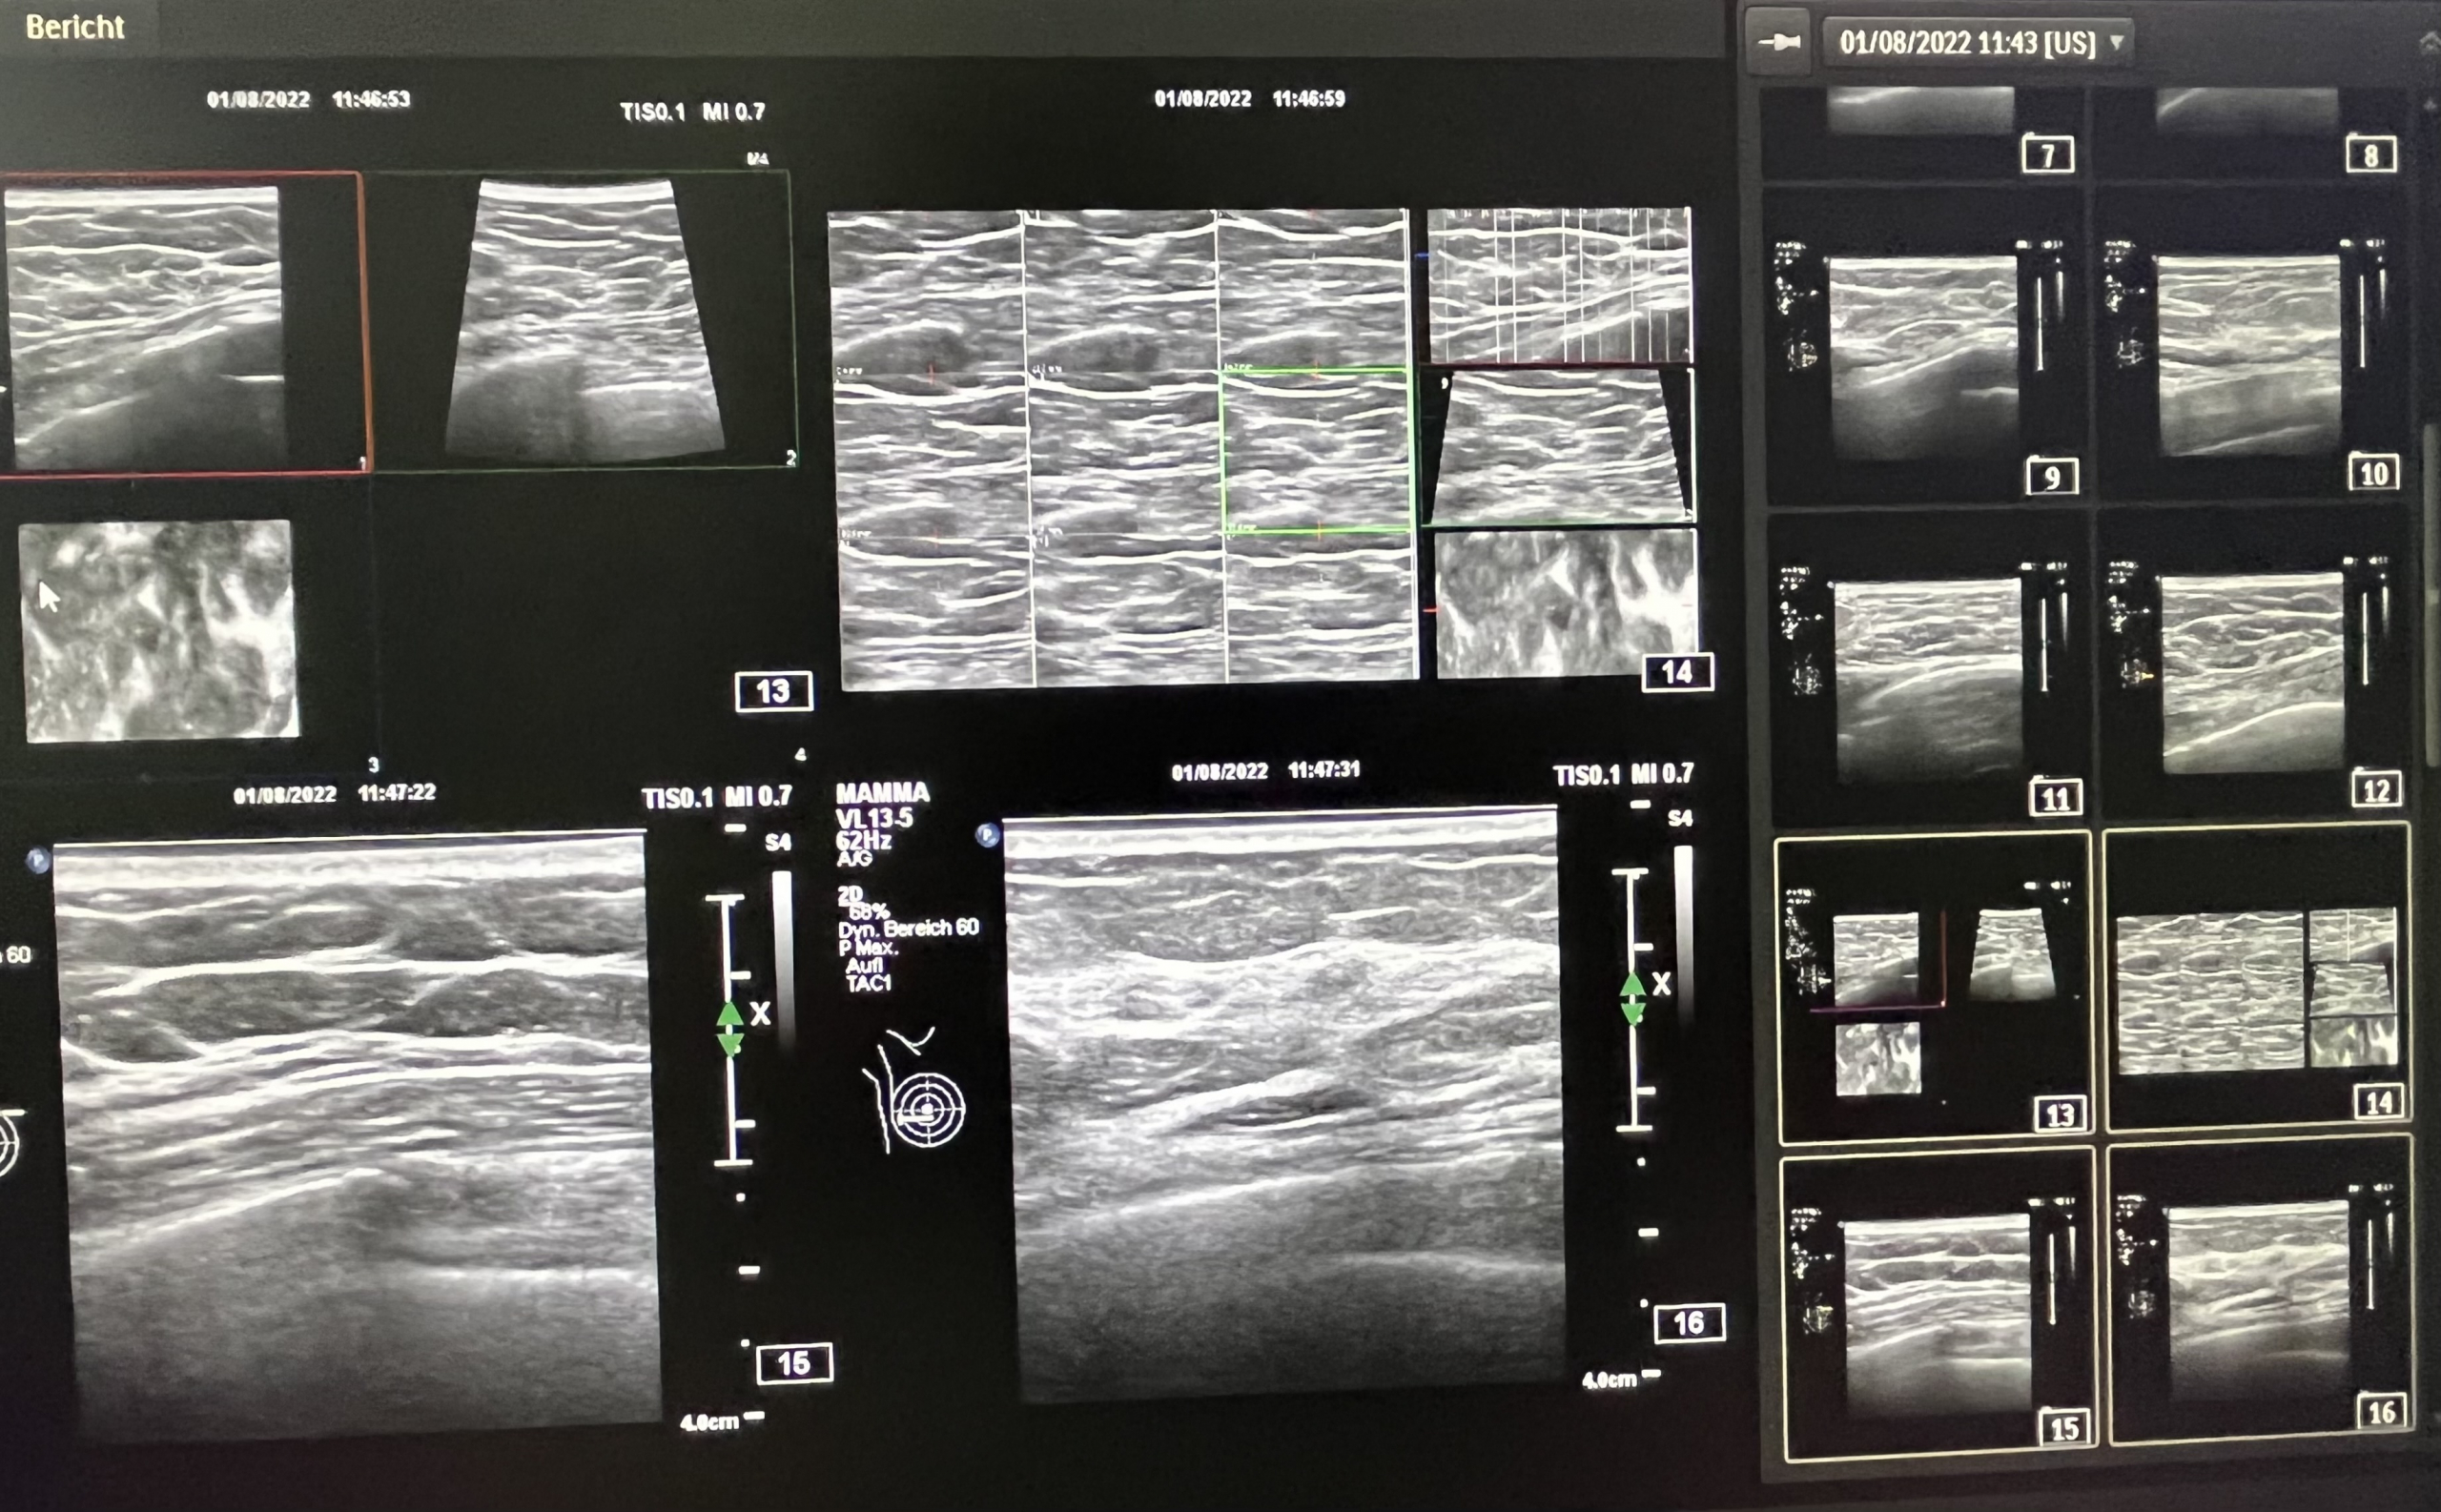

Our 4D ultrasound CT (multi slide imaging) technology can usefully complement – and extend – diagnostics according to guidelines as part of our extended cancer screening.

With our 4D ultrasound CT (multi slide imaging) technique, we can visualize pelvic organs (uterus, ovaries, bladder, intestines etc.), abdominal organs (liver, gallbladder, kidneys, spleen, pancreas, aorta, etc.), thyroid, etc., layer by layer (ultrasound tomography).

We are also successfully using our 4D ultrasound CT (multi slide imaging) technology in integrative breast cancer screening.

With our 4D ultrasound CT (multi slide imaging) technique, we can examine pelvic organs (uterus, ovaries, bladder, intestines etc.), abdominal organs (liver, gallbladder, kidneys, spleen, pancreas, aorta, etc.), thyroid, etc. without exposure to radiation.

We also successfully use our 4D ultrasound CT (multi slide imaging) technology in integrative breast cancer screening without exposure to radiation.